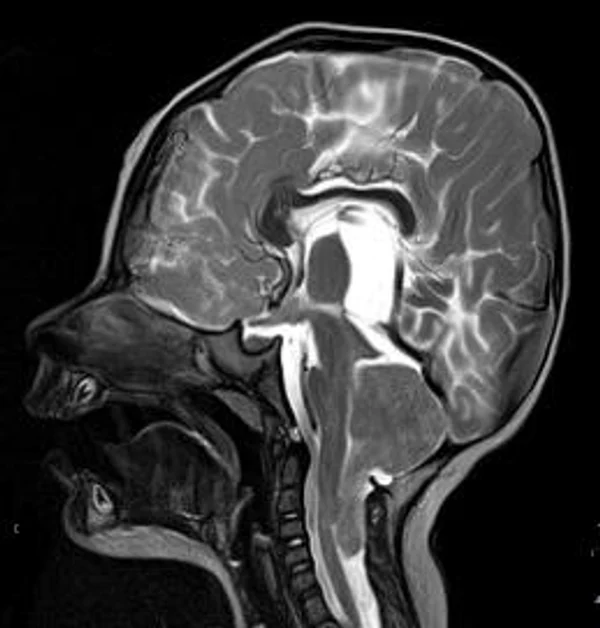

кисты, аномалии Денди-Уокера и др.Операции при внутричерепных кистах. В основном встречаются арахноидальные кисты различных локализаций и кисты сосудистых сплетений боковых желудочков. Пациентам с врождёнными кистами операции проводятся в следующих ситуациях: увеличении объема кисты в динамике, наличии клинических проявлений, компрессии и дислокации мозговых структур, наличии окклюзии ликворных путей. Нами используются 2 способа хирургического лечения кист: эндоскопическая перфорация стенок кист и открытая резекция кист. Открытая резекция кист проводится при ретроцеребеллярных арахноидальных кистах (рис. 2), при арахноидальных кистах межполушарной щели при отсутствии непосредственного контакта их стенок со стенками расширенных желудочков головного мозга и повторного увеличения кист средней черепной ямки после эндоскопической кисто-цистерностомии. Техника операции заключается в проведение краниотомии и максимальном иссечении стенок кист с созданием широкого сообщения кист с субарахноидальным пространством. Эндоскопические операции проводятся при арахноидальных кистах межножковой и пинеальной цистерн, арахноидальных кистах межполушарной щели при тесном контакте их стенок со стенками расширенной желудочковой системы (рис. 3), первично при арахноидальных кистах средней черепной ямки, а также при кистах сосудистых сплетений боковых желудочков. При арахноидальных кистах межножковой цистерны эндоскопически проводится перфорация стенок кисты, сообщая ее с просветом III желудочка и межножковой цистерной – эндоскопическая вентрикуло-кисто-цистерностомия (рис. 4). При арахноидальных кистах пинеальной цистерны проводится перфорация кисты в передне-верхних её отделах с созданием сообщения полости кисты с просветом III желудочка – эндоскопическая кисто-вентрикулостомия. С целью предотвращения облитерации сформированного отверстия иногда в полость кисты под контролем эндоскопа вводится стент перфорированный на протяжении (рис. 5, 6). Эндоскопическая кисто-цистерностомия выполняется при арахноидальных кистах средней черепной ямки. При этом создается широкое сообщение кисты с базальными цистернами. При кистах сосудистых сплетений боковых желудочков проводится их вскрытие в просвет боковых желудочков – эндоскопическая кисто-вентрикулостомия. При множественных кистах проводится их хирургическое сообщение между собой – интеркистосмия